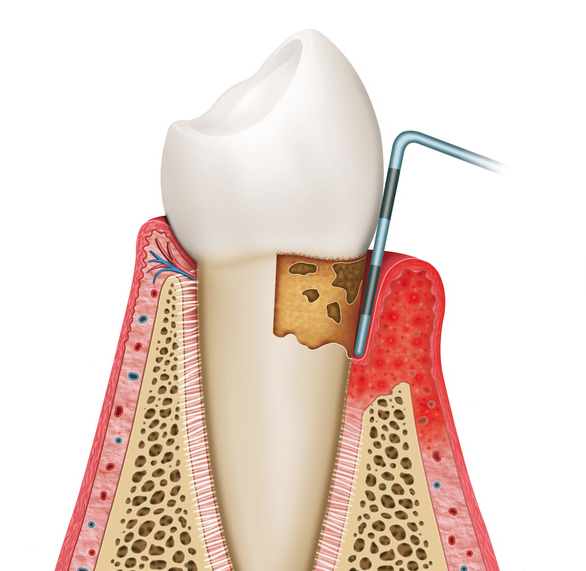

歯周病とは、歯の周りの組織(歯肉や歯槽骨など)が、プラークと呼ばれる細菌の塊内に存在する、歯周病菌に感染することによって引き起こされる、歯周組織の病気の総称を言います。

主な症状には、歯茎(歯肉)が腫れたり、出血したり、最悪な場合には歯自体が抜けてしまうこともあります。

歯周病にかかった場合、初期の段階では、ほとんど自覚症状が出ませんので、気づいていない人が多くいると思われます。

歯周疾患の原因によって、歯肉が赤くなったり、腫れたりするなどの炎症が現れます。

歯肉炎となった後、歯肉炎が進行することにより歯と歯肉の付着レベルが破壊されてしまい、歯周炎となります。

歯周炎が重症化することで歯を支えている歯槽骨の吸収が進行し、その結果、歯の動揺が増大することで最終的には歯の喪失にいたります。

歯ぐきの腫れ・知覚過敏が起こります。

強い口臭と、軽い歯のぐらつきが生じます。

咬めないほど歯がぐらつきます。